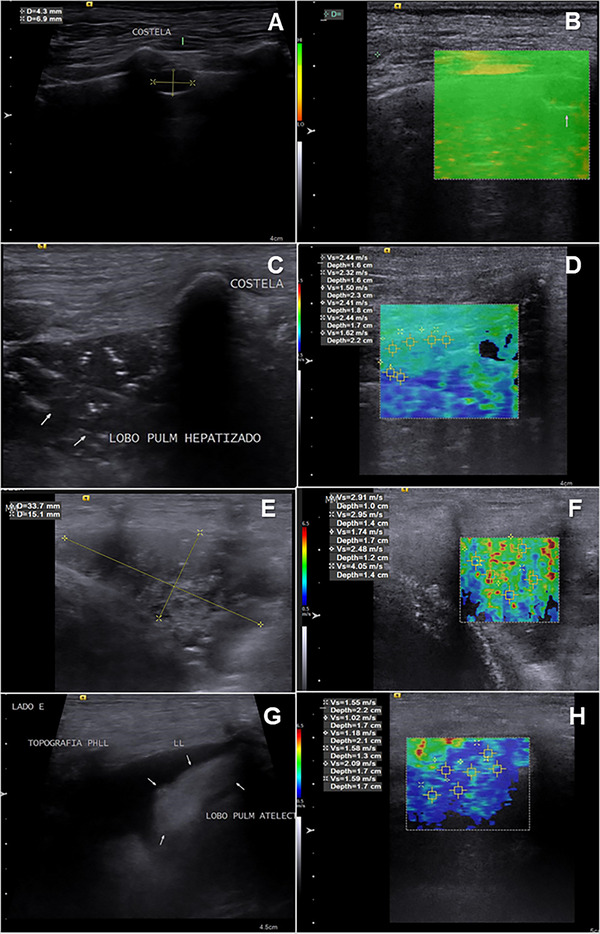

本研究旨在评估声辐射力脉冲(ARFI)弹性成像作为狗肺部病变诊断工具的应用。该研究包括在2020年至2022年期间被兽医教学医院放射科检查肺部病变的狗。肺病变的特征评估使用x线摄影作为定位的筛选工具,b超用于组织表征,随后进行定性(弹性图等级1-3)和定量(剪切波速- swv)弹性图评估。根据临床、超声、影像学、组织病理学和/或细胞学检查结果,将病变分为以下几类:实变、肺不张或肿瘤(结节和肿块)。26只狗符合资格标准,被纳入研究。在某些情况下,同一只狗有不止一种类型的病变,导致35个肺病变的评估:13个肿块,8个结节,8个实变,4个肺不张区。定量弹性成像评估显示,与实变(2.94±0.64 m/s)、结节(2.85±1.40 m/s)和肿块(3.13±1.45 m/s)相比,肺不张病变的刚度(1.48±0.35 m/s)较低,但由于良性病变数量有限,没有明确的诊断临界值。结果表明,ARFI弹性成像可以作为一种有价值的补充工具,与临床数据和传统成像技术一起评估狗的肺部病变。未来的研究需要更大样本量的良性肺实质病变,以进一步探索弹性成像预测恶性肿瘤的潜力。

This study aimed to evaluate the use of acoustic radiation force impulse (ARFI) elastography as a diagnostic tool for lung lesions in dogs. Dogs referred to the Radiology Department of the Veterinary Teaching Hospital between 2020 and 2022 for the detection of lung lesions were included in the study. The characteristics of the lung lesions were assessed using radiography as a screening tool for localization, B-mode ultrasound for tissue characterization, and subsequently, both qualitative (elastogram grades 1-3) and quantitative (shear wave velocity-SWV) elastographic evaluations. The lesions were classified based on clinical, ultrasound, radiographic, histopathological, and/or cytological findings into the following categories: consolidations, atelectasis, or neoplasms (nodules and masses). Twenty-six dogs met the eligibility criteria and were included in the study. In some cases, the same dog had more than one type of lesion, resulting in the evaluation of 35 lung lesions: 13 masses, 8 nodules, 8 consolidations, and 4 areas of atelectasis. The quantitative elastographic evaluation revealed lower stiffness in atelectatic lesions (1.48 ± 0.35 m/s) compared with consolidations (2.94 ± 0.64 m/s), nodules (2.85 ± 1.40 m/s), and masses (3.13 ± 1.45 m/s), although no definitive diagnostic cut-off value was established, due to the limited number of benign lesions. The results suggest that ARFI elastography can be a valuable complementary tool alongside clinical data and conventional imaging techniques in assessing lung lesions in dogs. Future studies with a larger sample size of benign parenchymal lung lesions are needed to further explore the potential of elastography for predicting malignancy.